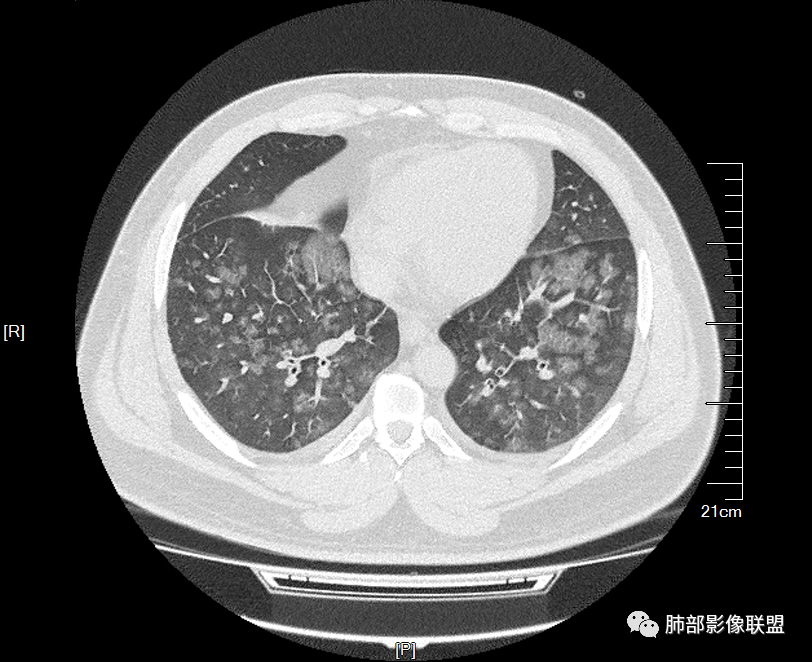

双肺多发弥漫性磨玻璃结节影,大小不一,形态不规则,部分融合,支气管未见明显扩张,部分血管束略增粗,叶裂胸膜增厚,临床有痛风,左足痛6天,考虑:1:痛风结节(一般实性结节,很少磨玻璃结节影)2:血管炎?3:病毒性肺炎(水痘-疱疹肺炎?)

年轻男性,痛风史,高血压史,肌酐高,左足痛6天入院。胸CT:双肺多发弥漫性磨玻璃结节影,大小不一,部分融合,上中下肺都有,中内带多,胸膜下少。部分血管束略增粗,小叶内间隔、小叶间隔增厚,下肺明显,左室大。叶裂胸膜增厚。临床有痛风,左足痛6天,考虑:心衰、间质性肺水肿?弥漫性肺泡出血?鉴别:MPA,肺肾综合征,痛风结节等。

多发GGO结节,边界清,以全小叶、小叶中心为主:

GGO背景

小叶间隔增厚,无明显重力趋势

少量积液,脂肪肝

这里有一点重力趋势

中轴间质稍增厚

细网格也明显

中轴间质增厚,小叶间隔增厚,小叶内间质增厚,部分重力作用,双侧对称,胸水,按理淋巴道回流受阻有

肺水肿类病变有

问题是腺泡结节如何解释?